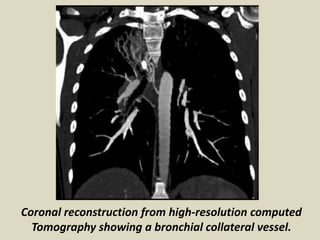

Coronal reconstruction from high-resolution computed

Tomography showing a bronchial collateral vessel.